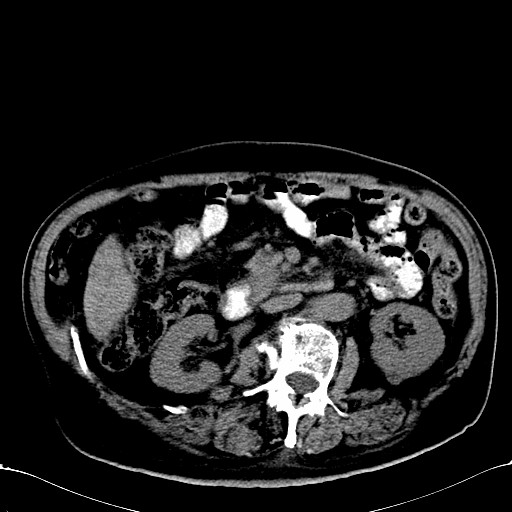

标题: CT28270:胰管扩张,肝多发占位 [打印本页]

标题: CT28270:胰管扩张,肝多发占位

患者,男,75岁。

肝脏多方低密度结节,边缘模糊,考虑多发转移,胰管明显扩张,建议增强扫描钩突情况

肝脏多发低密度灶,胰头似呈低密度,胰管扩张,建议增强,

胰管显著扩张,但胆总管未见扩张征象,不太符合胰头占位!考虑慢性胰腺炎.胃窦占位并肝内转移可能!mrcp胃镜增强一起上!